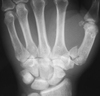

4

Q

Describe this fracture?

A

BENNETT

- Oblique fracture through base of the first metacarpal, with dislocation of the radial portion @ articular surface

- produced by direct force applied to end of metacarpal; dorsal capsular structures disrupted by dislocation; marked tenderness along medial base of thumb

• thumb spica x 4 weeks

How well did you know this?